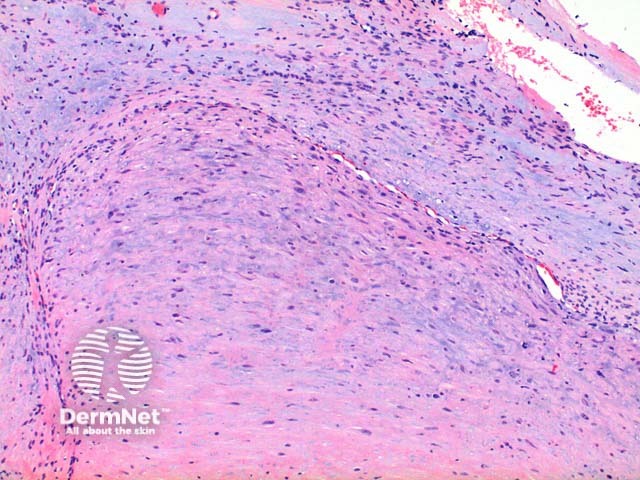

Low power view of myofibroma demonstrates a well defined multinodular tumour arising in the deep dermis or subcutis (Figure 1). Also at low power a branching ‘staghorn’ like pattern of blood vessels can be seen between the tumour nodules (Figure 2). Areas of calcification can often be seen (Figures 2, 3 and 5). The tumour nodules are comprised of a spindle cell proliferation with short plump nuclei (Figures 4,5 and 6). A basophilic tinge in the spindled peripheral component of the nodules is evident (Figures 7 and 8). Sclerotic collagen in the centre of the tumour nodules gives a biphasic appearance to the tumour (Figure 9).